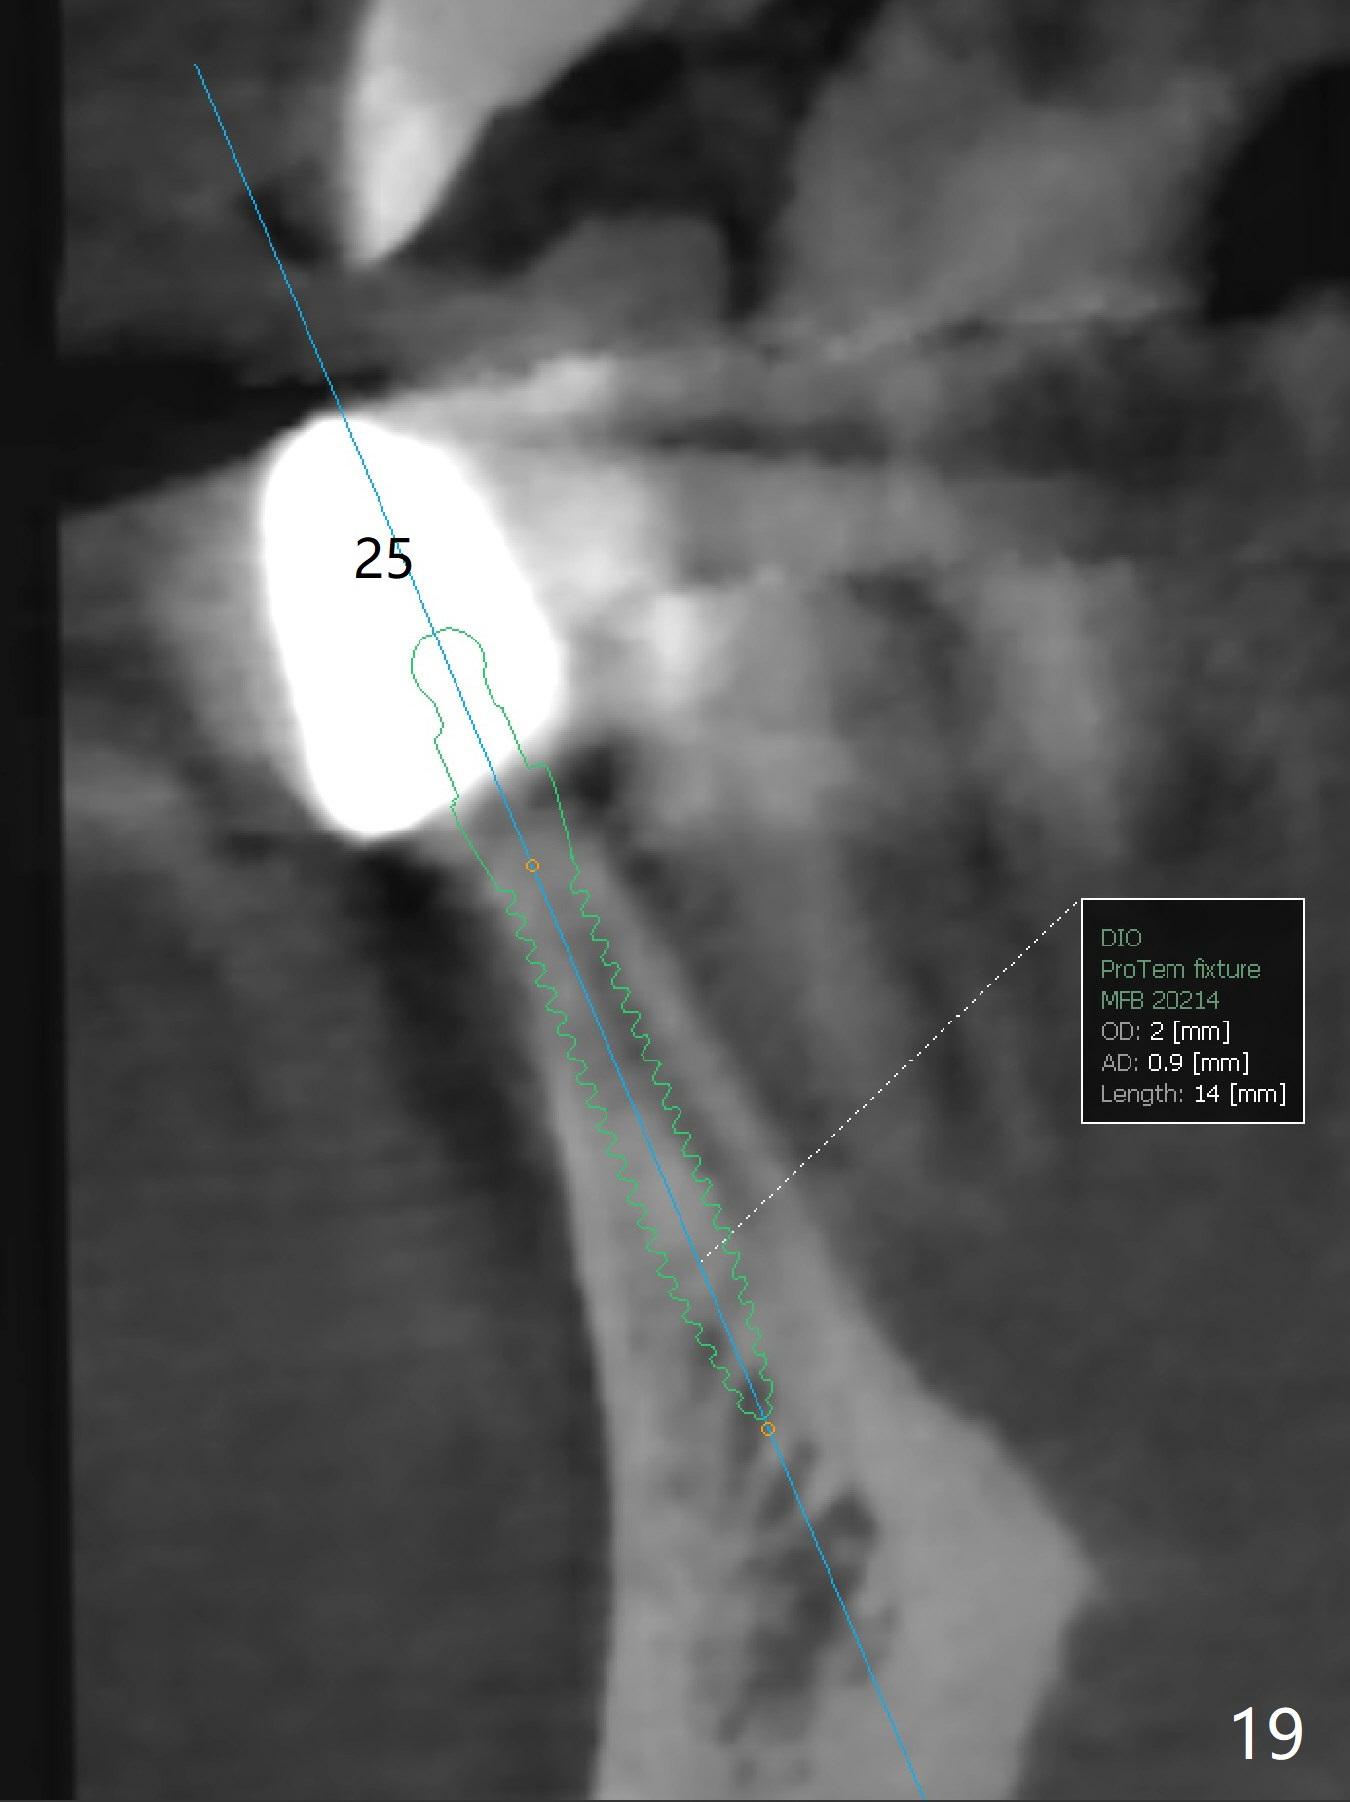

The infection persists at #26 four years 8 months post cementation (Fig.16 *). CBCT is taken. In fact the implant at #26 was placed lingual (Fig.17), while that at #24 buccal (Fig.20). The 2nd option is to remove the implant at #26 and place a 2 mm one at #25 (Fig.18,19). Fabricate a 3-unit cantilever FPD. Take 5x5 cm CT with 1.2 mm drill in place for 10 mm. Change the trajectory and position if necessary.